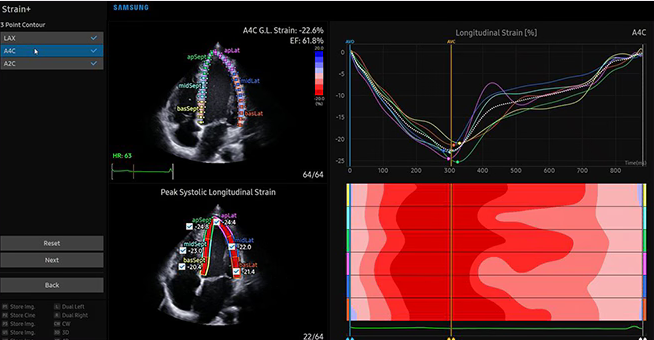

„Tryb obrazowania niedopplerowskiego MV-Flow umożliwia bezpośrednią

wizualizację w czasie rzeczywistym złożonej dynamiki przepływu krwi i tym

samym ocenę mikro(!) unaczynienia w zmianach ogniskowych, które nie jest

dostępne w aparatach starszych generacji i niskiej klasy z uwagi na ograniczenia

związanych z technikami dopplerowskimi.”